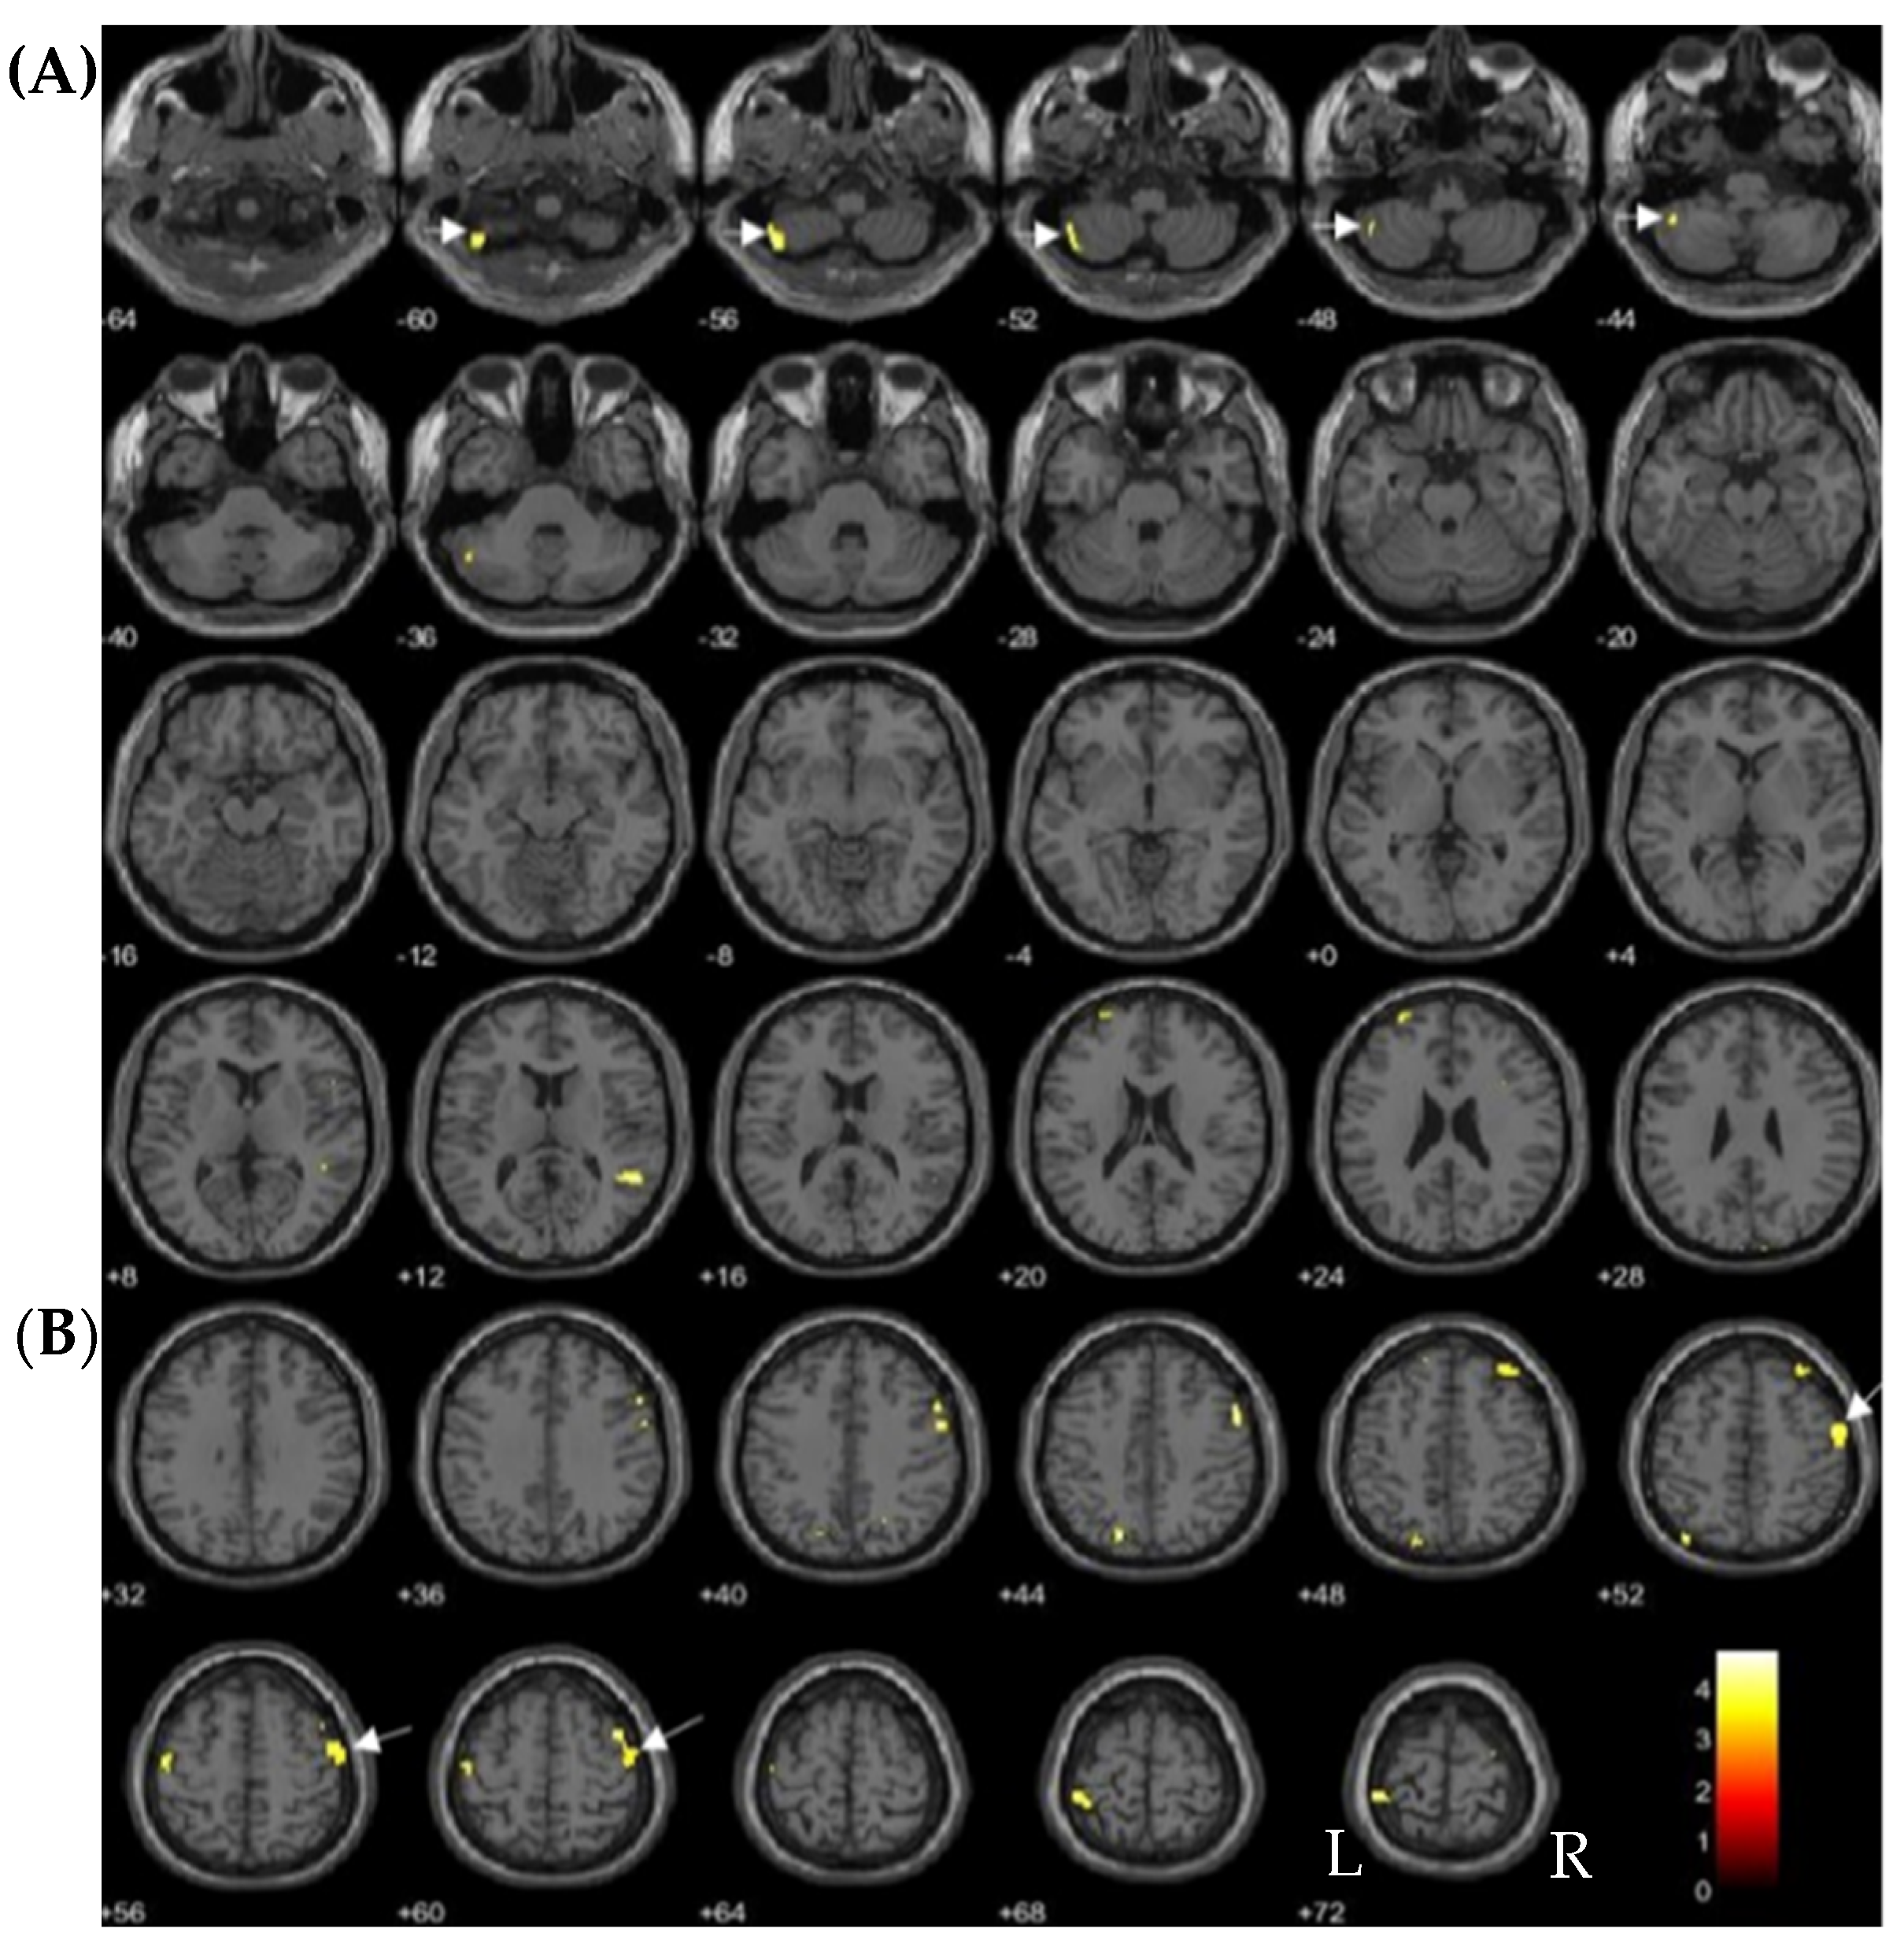

| Dioxin Congeners | Brain Regions | No of Voxels in Each Cluster (k) | Peak Z Scores | MNI Coordinates | ||

|---|---|---|---|---|---|---|

| x | y | z | ||||

| Inverse correlations | ||||||

| TCDD | Anterior temporal cortex | 905 | ||||

| (Left medial temporal pole) | 3.81 | −41 | 20 | −38 | ||

| (Left fusiform gyrus) | 3.90 | −27 | 8 | −47 | ||

| TEQ-PCDDs | Left medial temporal pole | 333 | 3.63 | −39 | 21 | −38 |

| Positive correlations | ||||||

| 1,2,3,4,7,8-HxCDD | Left cerebellum lobule VII | 373 | 3.87 | −42 | −60 | −57 |

| Right middle frontal gyrus | 505 | 3.86 | 41 | 6 | 60 | |